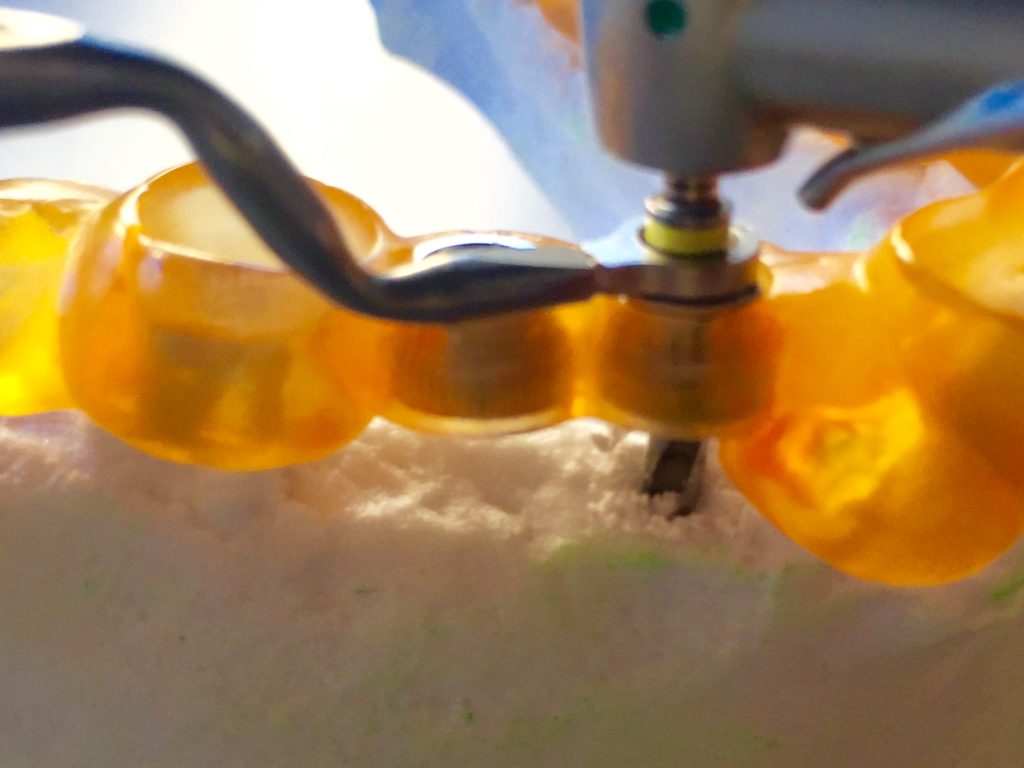

Autores: PRÓLOGO Asimismo, desde el punto de vista pedagógico, el profesional nobel en la materia tiene a su alcance la posibilidad de corregir cualquier posición implantaría en el ordenador, planear los provisionales y plasmarlos en la bio réplica antes de tocar al paciente a operar. Todos estos razonamientos nos llevan a presentar un caso de condiciones muy favorables para poner en práctica estos métodos como primer acercamiento a una Odontología Digital de alta calidad, con medios informáticos, que ya están presentes en la profesión de hoy en día, y será la protagonista única del futuro. Por otro lado, después de numerosos estudios que nos llevan a plantear el “gap” entre implante y pilar(abuttment), como principal responsable de la periimplantitis dado que la microbiota presente en el mismo es imposible de limpiar y en su presencia la cortical ósea reacciona reabsorbiéndose, nos ha llevado a utilizar implantes monobloc ya que los ejes implantarios y protéticos coincidían, y nos permitían su uso. Además, el circonio, ha mostrado a la luz de estudios muy recientes, una preservación y adhesión de los tejidos blandos superiores al titanio, tanto en su tratamiento de superficie de la rosca como a nivel gingival. DESARROLLO Paciente varón de 68 años, con antecedentes de radio/quimioterapia cinco años antes, con Rehabilitación Oral de los cuatro cuadrantes, con una Oclusión Mutuamente Compartida conservada, (REF.8) la que fracasa en el cuadrante 4, 19 años después. El mismo presentaba un puente de porcelana sobre circonio con pilares en 44 y 47, reemplazando el edentulismo de 45 y 46. Se produce la fractura del PM del 44, y ante una endodoncia antigua y corta, se decide implantar las zonas edéntulas, conservando temporariamente los pilares, hasta producida la oseointegración, para entonces también exodonciar el 44. DIAGNÓSTICO Tomamos impresiones del maxilar antagonista, Arco Facial Estático y realizamos montaje del mismo mediante la sistemática ARTEX. Producimos la relajación del músculo Pterigoideo Externo, para obtener la ORC (Oclusión en Relación Céntrica) mediante el método de Laminillas de Long, basado en el concepto de INERVACIÓN RECÍPROCA. Esto nos permitirá montar el maxilar inferior, tanto en su forma de: La primera para practicar la cirugía guiada y comprobar su eficacia, y el modelo de yeso para ser escaneado y confeccionar la GUÍA QUIRÚRGICA. La Biorréplica la obtenemos transformando los archivos DICOM que nos da el CBCT en archivos STL, y a partir de ellos, mediante una tecnología de PROTOTIPADO RÁPIDO, la obtención de un objeto físico en 3D a través de la aglutinación selectiva de una sucesión de capas de polvo. Procedemos a montar la biorrèplica y el modelo de yeso del caso. Podemos verificar la exactitud de las medidas del hueso residual en la bio réplica y compararlas con el scanner. Arrojando un resultado de 8,5 mm de cortical externa a cortical externa. Pudiendo también medir la distancia hasta el dentario. y comparar gracias a la ventana lateral de la biorréplica Dándonos 22mm de distancia. Con lo cual deducimos que implantes de 4,1mm por 12 mm serán perfectamente rodeados de hueso. Medimos también la distancia desde oclusal del antagonista, hasta el hueso desnudo. Lo mismo que, mediante la utilización de la guía radiológica, con un material radiolúcido colocado en gingival de la misma, podemos medir la altura de la encía. Con lo cual podemos calcular la altura del pilar. Es entonces cuando con el programa COC Diagnostix se realiza la programación final: Obteniendo no solo la ubicación, largo, ancho y ángulo de los implantes sino también los provisionales mediante CAD CAM. Ya entonces podemos hacer la práctica quirúrgica en la bio réplica, mediante la guía quirúrgica, instalando los implantes de prueba que no serán los de circonio, ya que la casa no cuenta con ellos, pero si otros de las mismas dimensiones. TRATAMIENTO Entramos ya en la cirugía propiamente dicha. Antisepsia de la zona a operar y zonas anexas. Comprobación del perfecto ajuste e inmovilidad de la G.Q. en boca durante la cirugía. Marcado de la encía y perforación de la cortical. Visión a través de la Guía de la mínima intervención anterior. Comprobación sin Guía. Incisión mínima mesio distal, para apartar y conservar encía queratinizada. Secuencia de drills, perforando a profundidad requerida Observación del Mínimo Trauma Implantes Strauman de Zirconio Monoblock en blíster y montádo en contrángulo reductor. Instalación controlando torque con contrángulo reductor. Comprobación clínica. Comprobación Radiográfica y con Guía. Toma de impresiones, y armado de modelos con técnicas de pasividad protética. Montaje. Resultado de las provisionales ejecutadas por CAD CAM Al no estar conformes con el resultado decidimos desechar dichas provisorias y optar por repetirlas. Nuevas provisorias realizadas mediante encerado convencional. Estado de los tejidos blandos. Provisorias en boca. Oclusión de Estímulo Inmediato. Ref.10: Carga inmediata .Alberto y Diego Bechelli. Comprobación mediante CBCT post operatorio Componentes del equipo (En la próxima presentación, mostraremos las coronas definitivas de porcelana sobre circonio, y la desoclusión provocada por una OCLUSIÓN MUTUAMENTE COMPARTIDA, sobre estos implantes y otros seis mas) REFERENCIAS

FIG: 1-2-3-4

FIG: 14-15-16-17-18-19-20

FIG: 21-22-23-24-25-26

FIG: 35-36-37-38-39-40-41

FIG:42-43-44-45-46

FIG:50-51-52-53-54